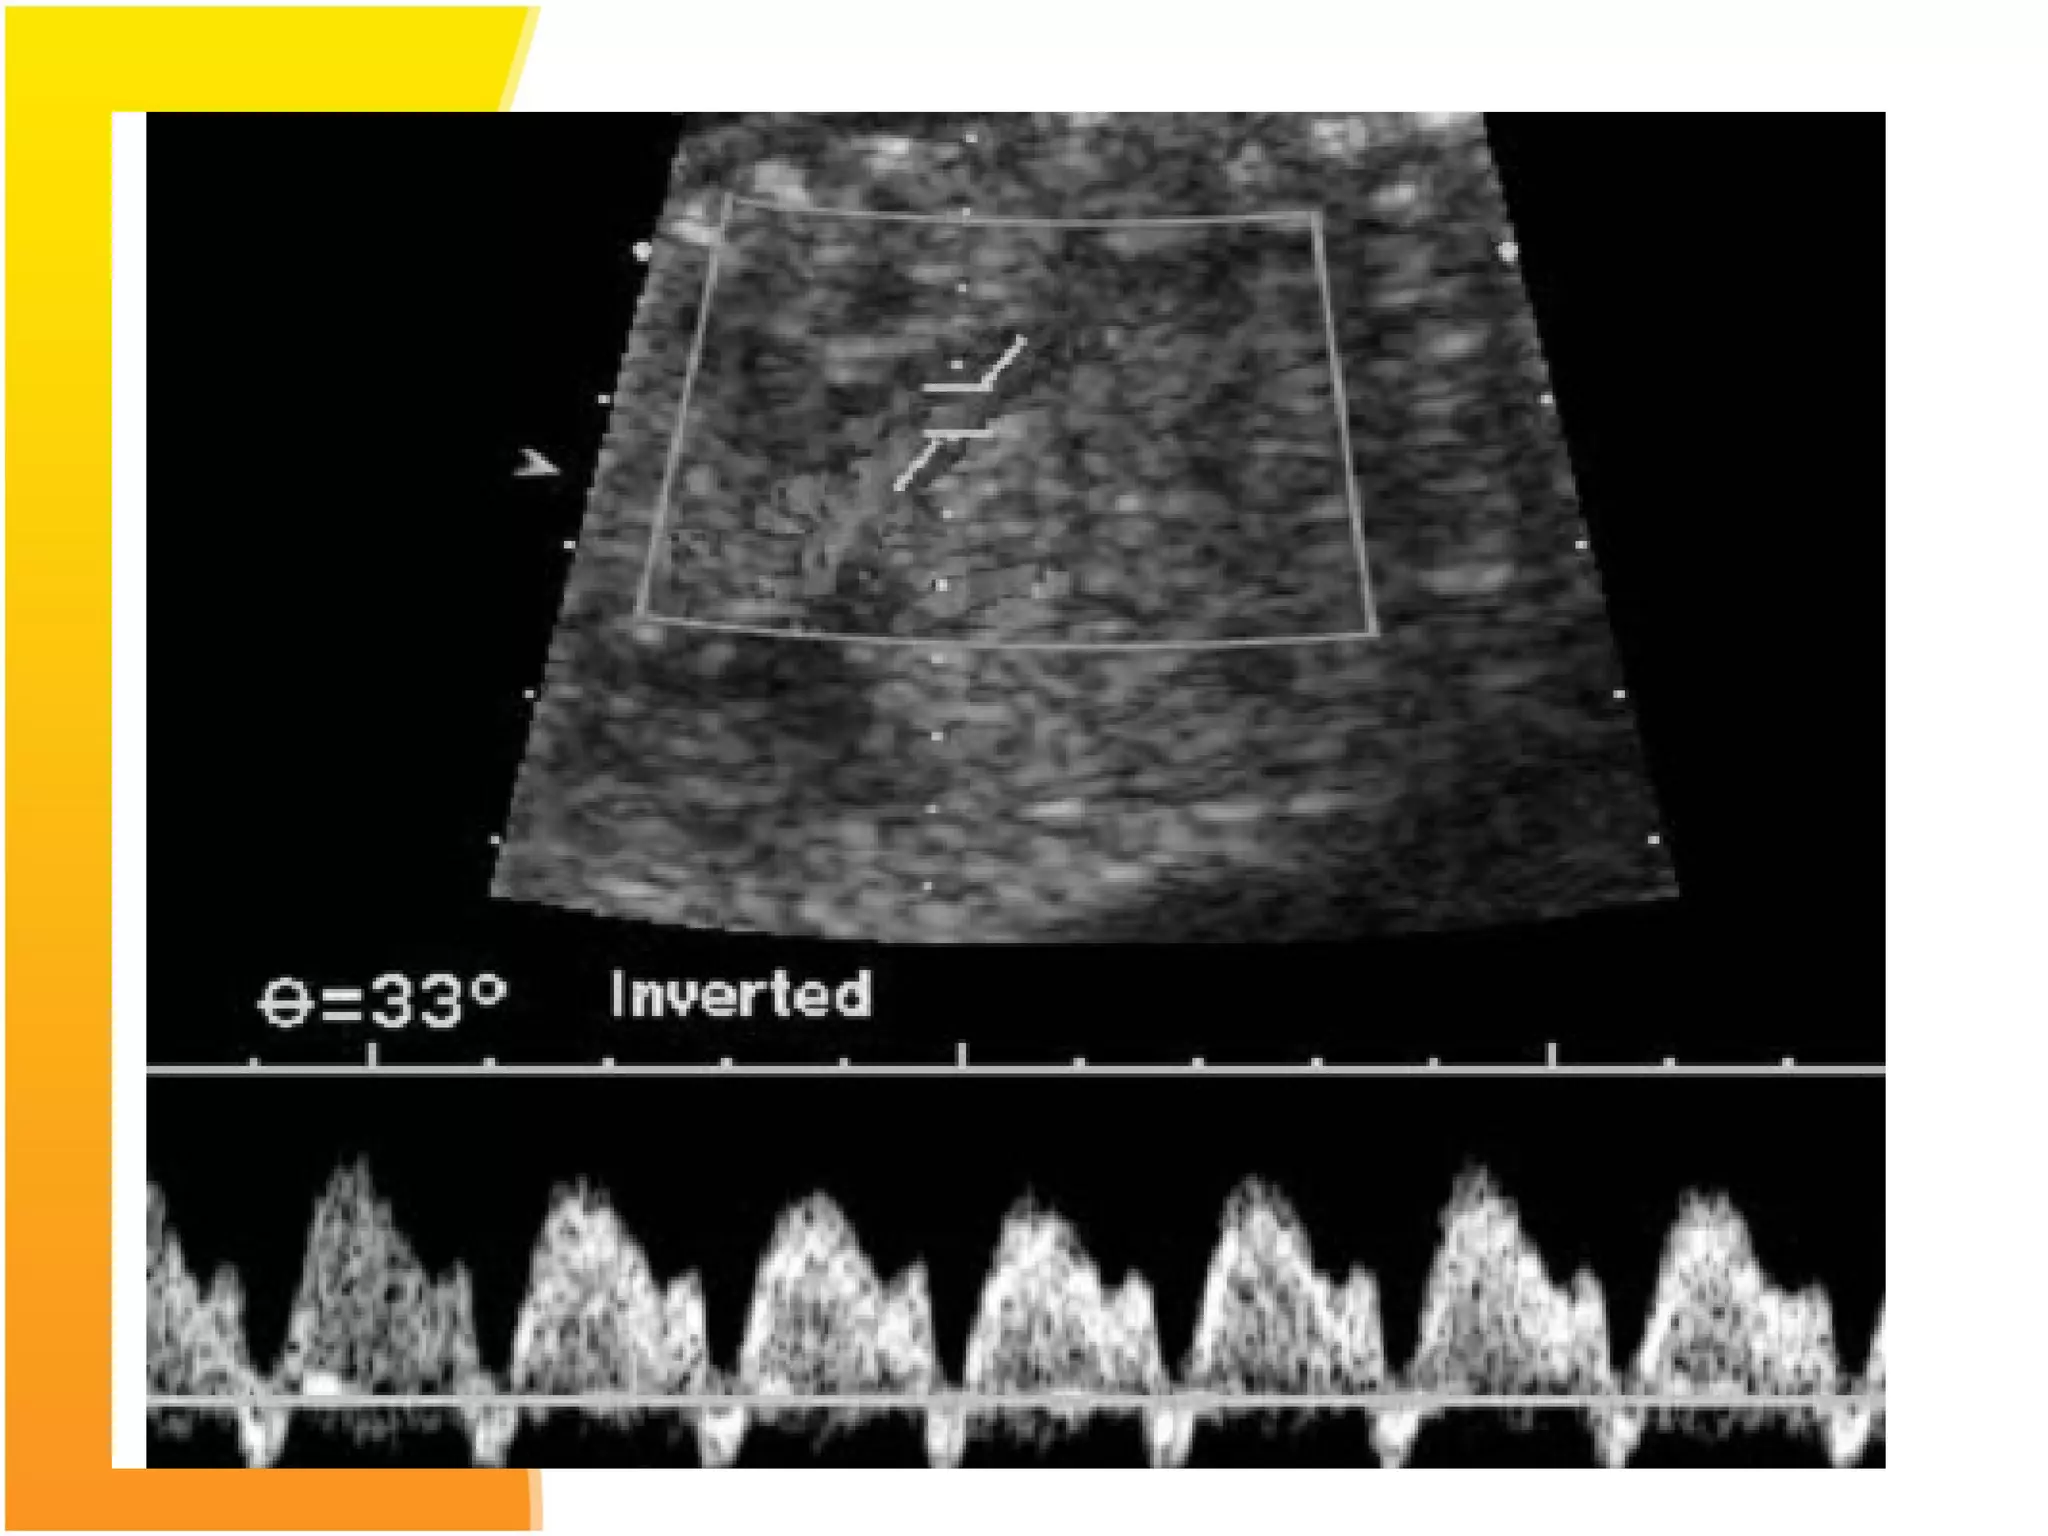

Middle cerebral artery Doppler- in a

normal fetus has relatively little flow

during diastole. Increased resistance to

blood flow in placenta results in

redistribution of cardiac output to

favour cardiac and cerebral

circulations leading to increased flow

in the diastolic phase with decreased

S/D ratio.

Normal Flow velocity waveforms of middle Cerebral Artery

Doppler

Cerebral artery doppler

 Cerebral/Placental ratio: ratio between MCA PI

and umblical artery PI is more sensiive predictor

than either MCA and umblical artery velocimetry

alone to detect redistribution of blood flow.

Cut off values below 1.0 to 1.1 are considered to be

diagnostic of brain spairing effect.

• MCA peak systolic velocimetry: is good indicator

of fetal anaemia and is less useful in IUGR.